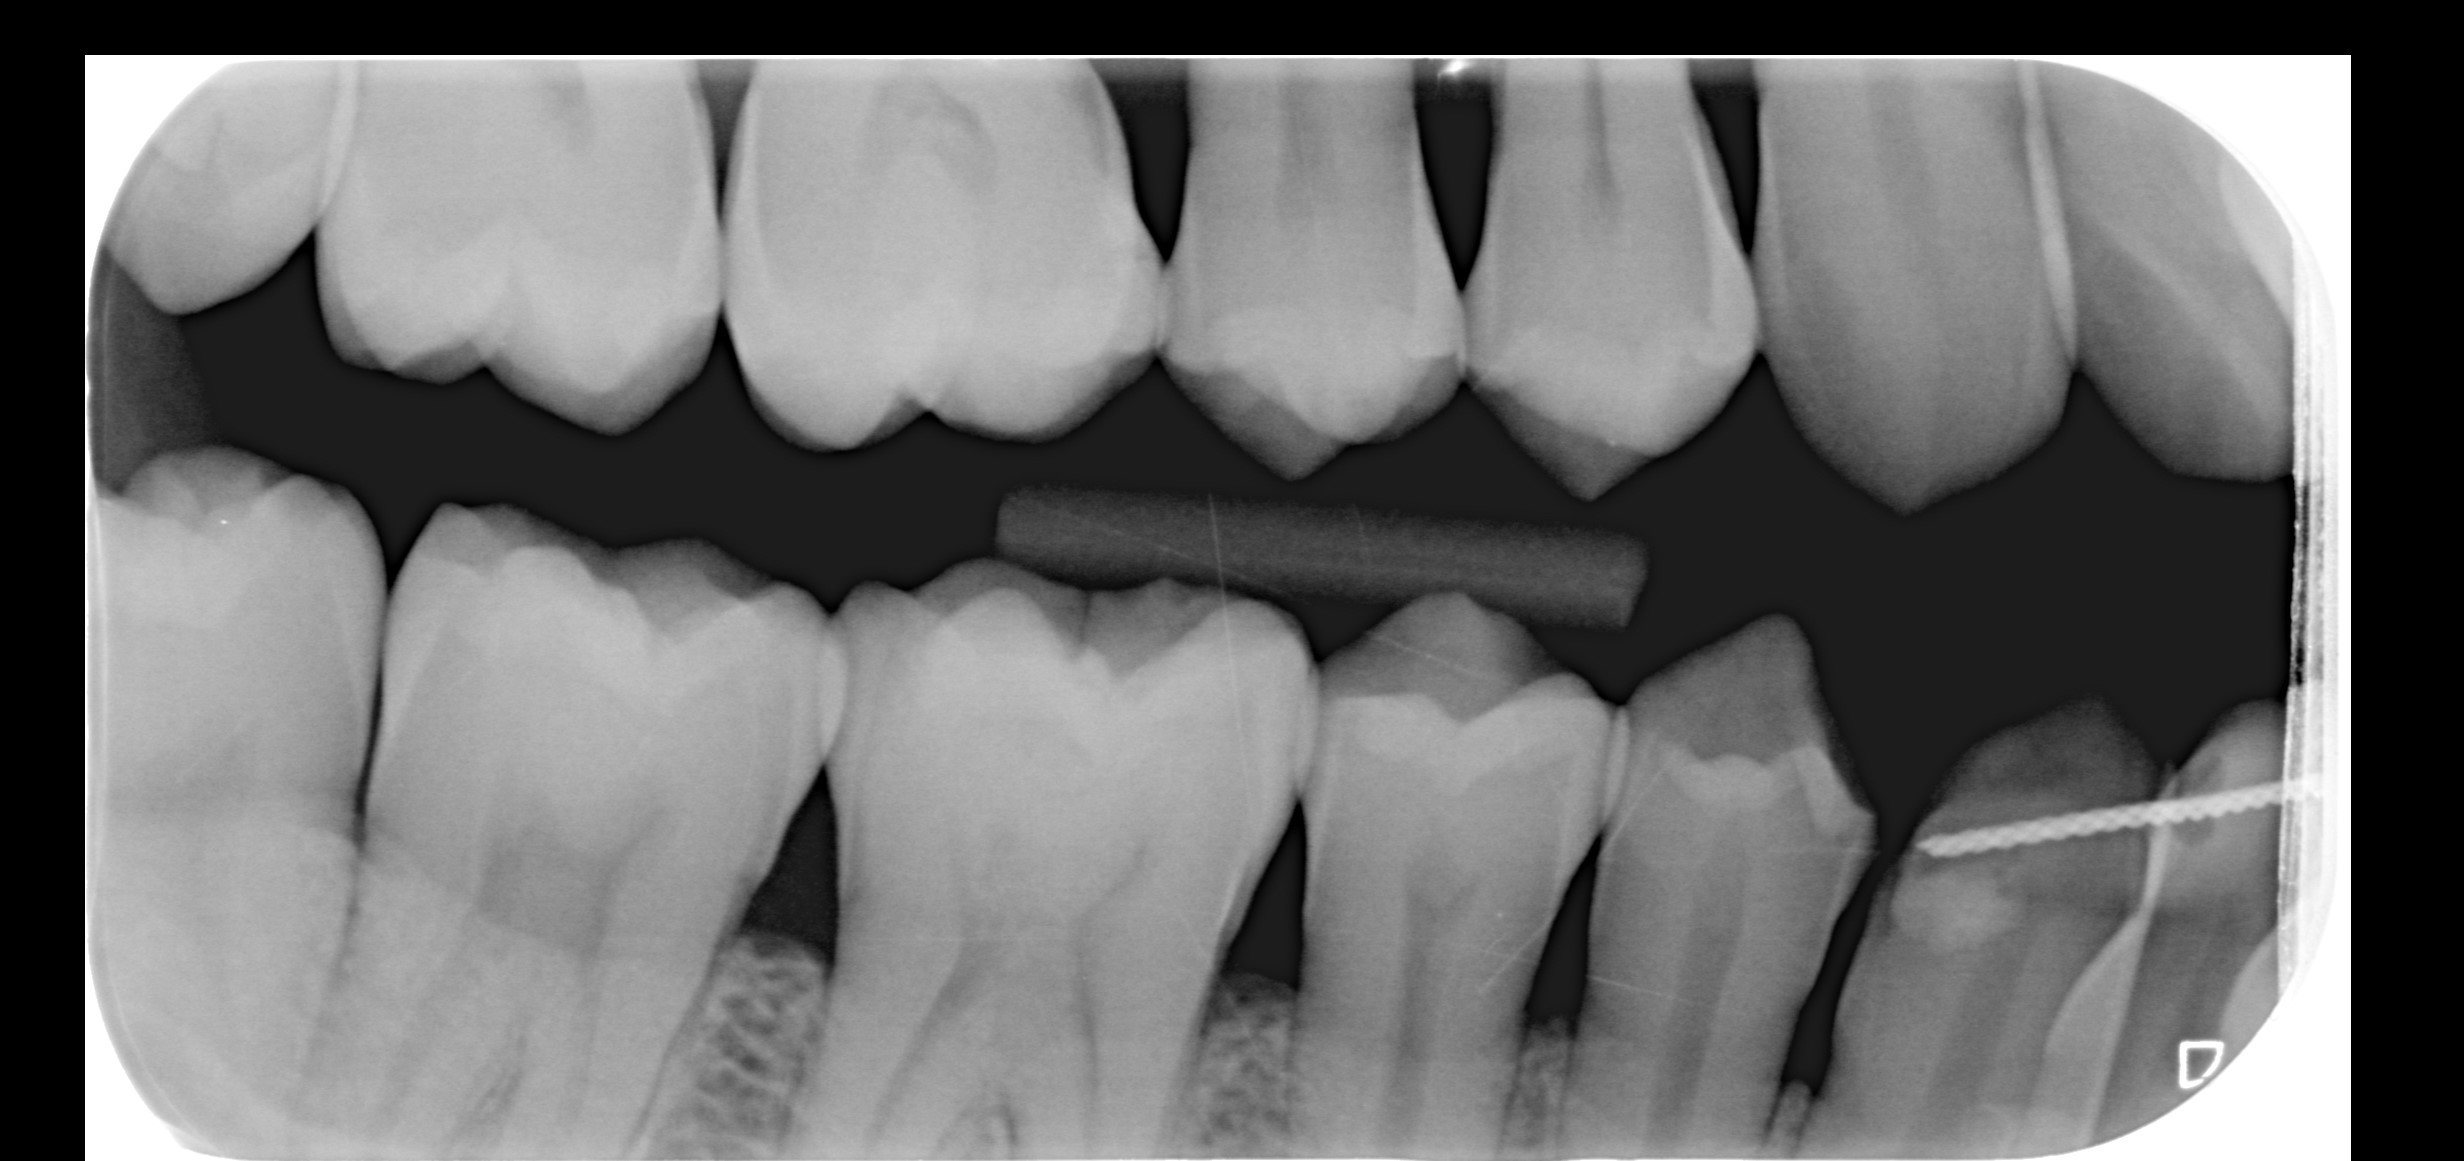

Ik had in april dit jaar al een vraag gesteld in dit forum over mijn mogelijke erosie, u gaf toen aan dat er enige slijtage was. Ik heb totaal geen idee hoe het kan zijn ontstaan, omdat ik mijn hele leven al zowat geen suikers of prik of zure dranken nuttig. Mijn tandartsen en mondhygienisten hebben er ook NOOIT wat over gezegd. Hierbij een foto van 2015 en 2025 onderkaak tanden. Ik zie in die 10 jaar geen verschil. Is het echt flinke slijtage of valt het mee? Wat betreft mijn botniveau, heb ik inderdaad te horen gekregen dat er sprake is van lichte botafbraak, ik gebruik nu elke dag ragers. Heb in het verleden ook een beugel gehad, zou dat ook voor veranderingen in het bot kunnen zorgen? x-fotos van mijn rechter kaak uit 2010 en eind 2024.

Bovenste x-foto lijkt meer dan onderste foto maar kan ook aan de inschiet richting liggen.

Lijkt de erosie meer te zijn bedoel je? de tweede foto is iets warmer dan de eerste omdat het twee verschillende camera's zijn, maar ik zie persoonlijk geen verschil, hoop dat het in ieder geval gestopt is. En wat betreft de x-foto's, de tweede is recent en de eerste is van 14 jaar geleden. En wat betreft mijn pericoronitis, pijn is volledig weg, maar het tandvlees daar is nog zacht en niet strak tegen de verstandskies aan. Is dit een probleem en gaat dit nog over? Ga mijn verstandskiezen in 2026 wel verwijderen, maar wil wel weten of het een probleem is dat het tandvlees daar zacht is.